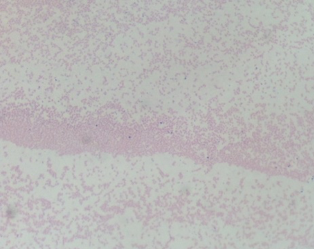

Gram